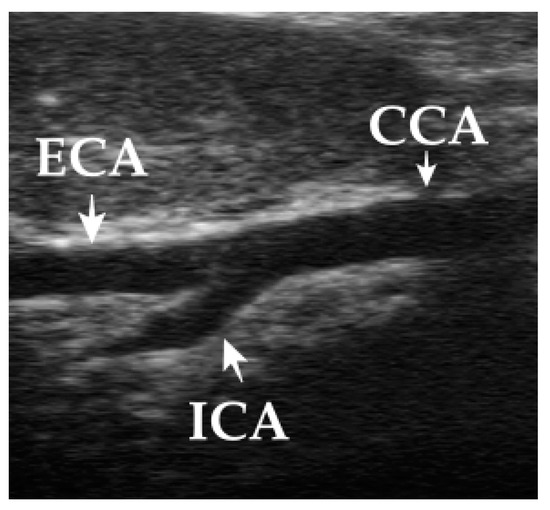

3.3. Evaluation of the CCA

3.4. Evaluation of the ECA

3.5. Evaluation of the ICA